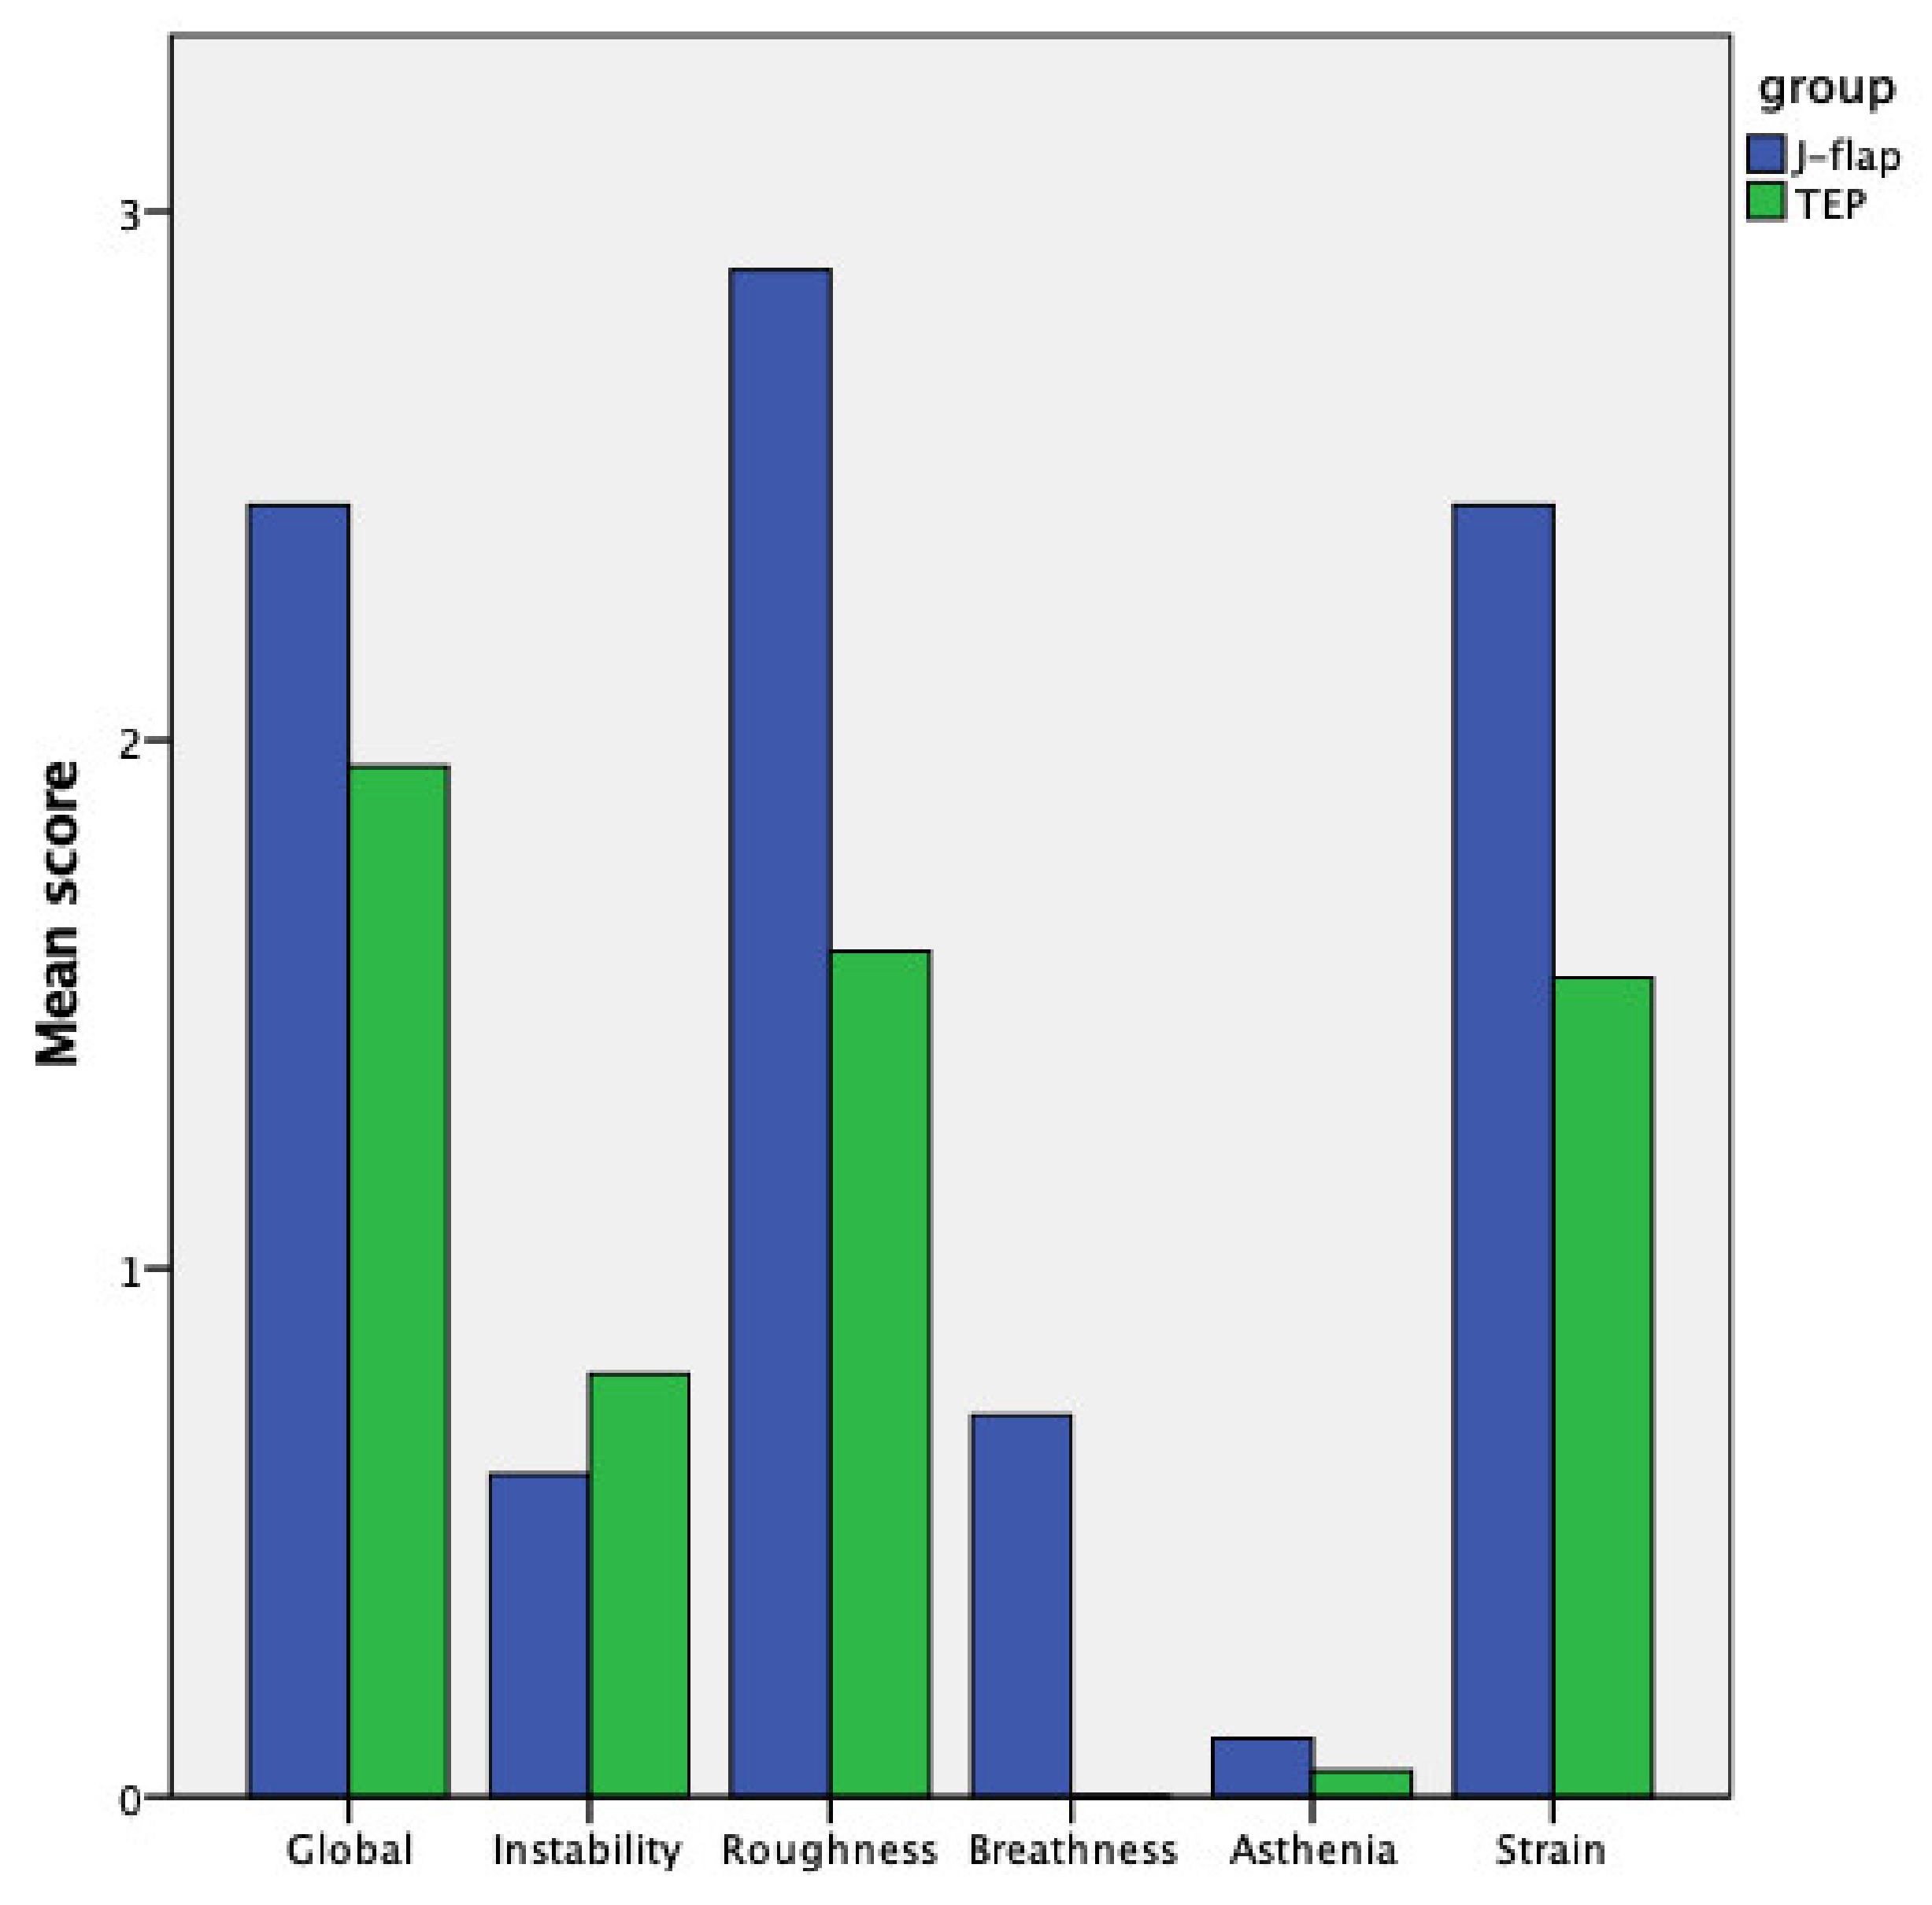

| Voice quality Globally | 2.446 ± 0.85 | 1.95 ± 0.82 | 0.04 |

| Voice quality Instability | 0.61 ± 0.97 | 0.80 ± 1.00 | 0.43 |

| Voice quality Roughness | 2.89 ± 0.47 | 1.60 ± 0.68 | <0.001 |

| Voice quality Breathiness | 0.72 ± 1.22 | 0.00 ± 0.00 | 0.01 |

| Voice quality Asthenia | 0.11 ± 0.32 | 0.05 ± 0.22 | 0.49 |

| Voice quality Strain | 2.44 ± 0.92 | 1.55 ± 1.05 | 0.009 |